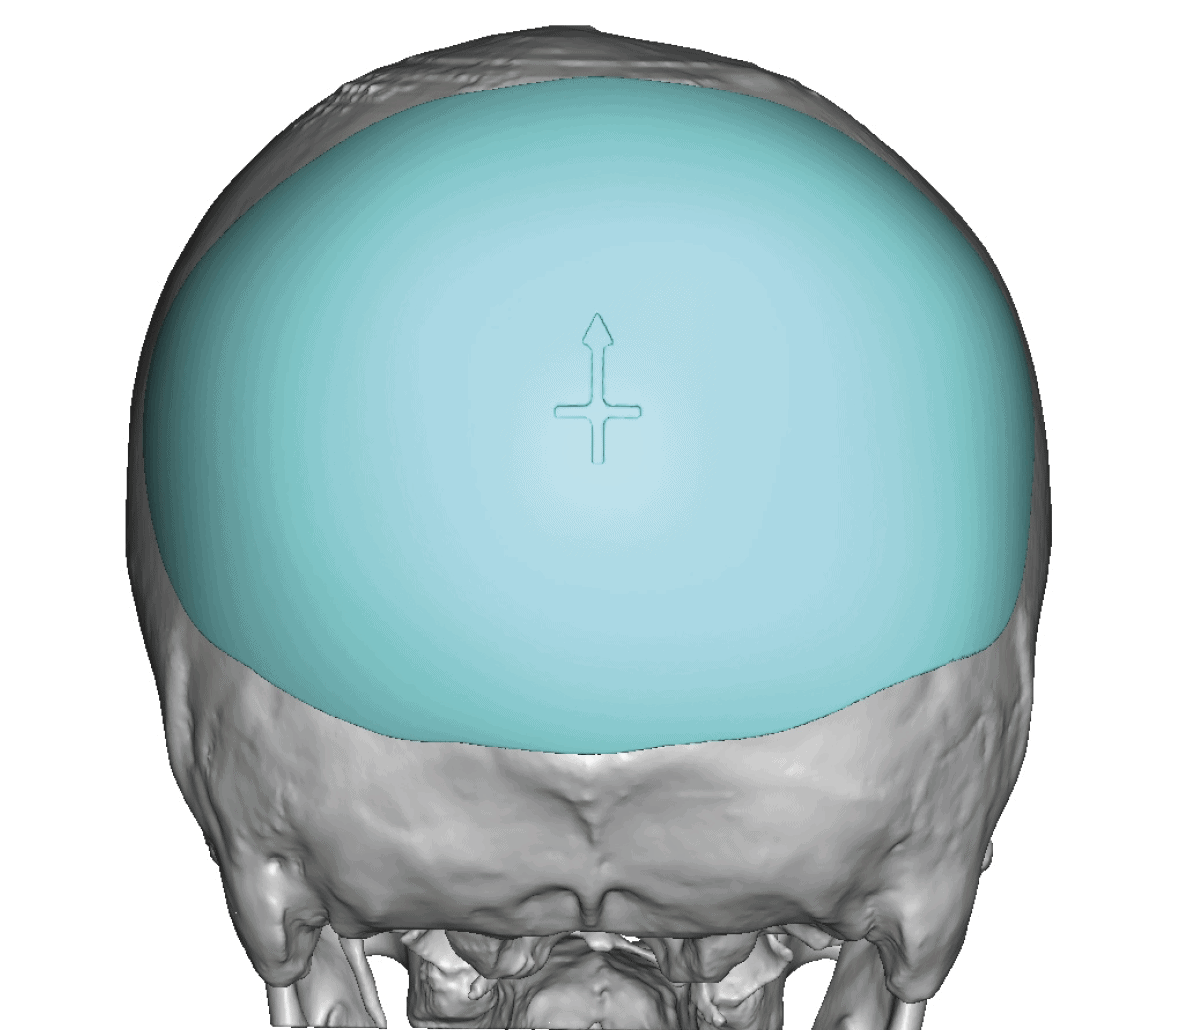

Patient 49

Desire for further skull augmentation after a primary skull implant.

Five years after an initial custom skull implant placement a new custom skull implant that increased the volume by 35% was placed.

Desire for further skull augmentation after a primary skull implant.

Five years after an initial custom skull implant placement a new custom skull implant that increased the volume by 35% was placed.